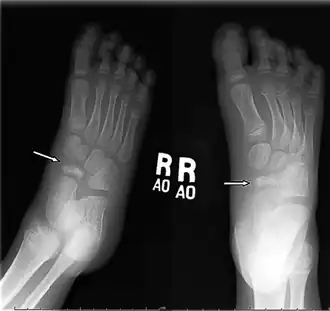

Navicular bone with avascular necrosis arrows

Diagnosis is made on the basis of history and a high index of suspicion. On examination there is tenderness to palpation on navicular head. Radiographs reveal typical changes of increased density and narrowing of the navicular bone.An X-ray of both feet is used to diagnose disease.